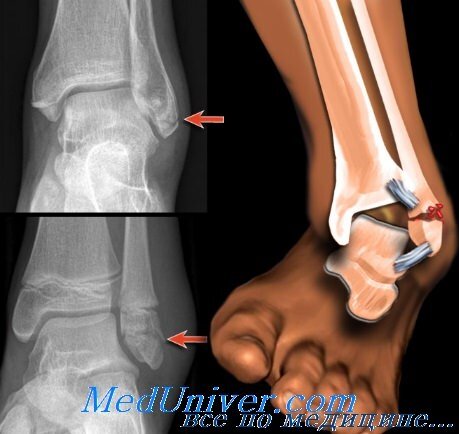

Чаще всего перелом голеностопа возникает при нагрузке, превышающей максимальную прочность сустава. Перелом характеризуется гематомами, болью при ходьбе или любом движении сустава, головокружением, отёком. Травма достаточно серьёзная, можно выпасть из спорта как на пару недель, так и на пару месяцев. Чтобы уменьшить риск перелома рекомендую уделять разминке голеностопа отдельное место, составить комплекс упражнений и купить хорошие кроссовки(такие, чтобы держали пятку).